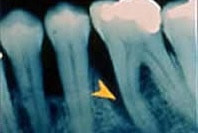

Im Frühstadium ist Parodontitis schmerzlos und lässt sich so am besten behandeln. Deshalb ist eine regelmäßige zahnärztliche Kontrolle wichtig. Bei der zahnärztlichen Untersuchung misst der Zahnarzt die Taschentiefen. Zusätzlich können Röntgenaufnahmen dabei helfen, einen möglichen Knochenabbau sichtbar zu machen. Die häufigsten Symptome sind bei voranschreitender Gingivitis:

Bei länger bestehender Gingivitis greift die Entzündung vom Zahnfleisch auf den die Zahnwurzel stützenden Kieferknochen über und beginnt diesen abzubauen. Es bilden sich zunächst Zahnfleisch-, dann Knochentaschen, in deren Tiefe zahnsteinartige Ablagerungen den Entzündungsprozess weiter verstärken können.

Fortgeschrittene Parodontitis mit tiefer Knochentasche